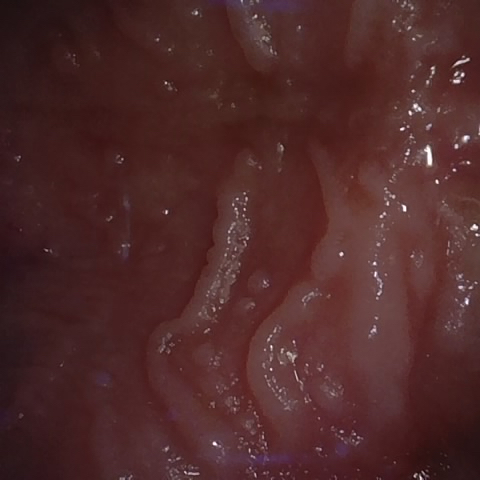

NHD39174

Annotated as "Good"

Original Image Rendering Image